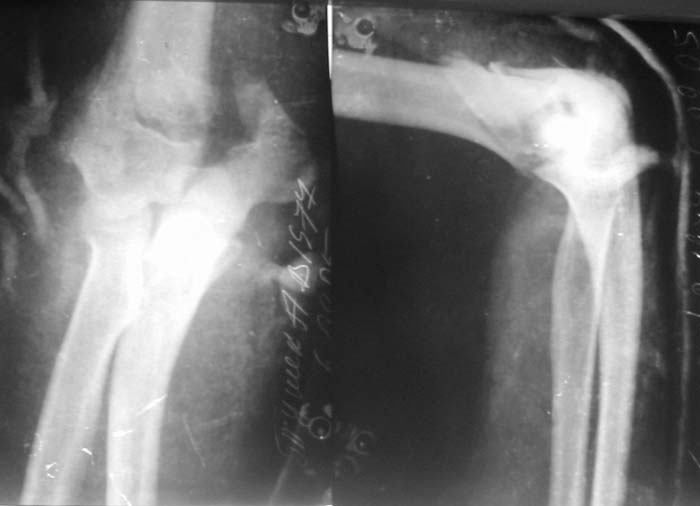

Женщина 42 лет, операция через неделю после перелома.

Д-з - открытый перелом мыщелков со смещзением и локтевой кости

без смещения - падение с лошади.

До операции снимки не очень, тем более в гипсе.

Остеосинтез закрытый (если так можно выразиться), т.е. без

разрезов. Длительность операции - около 1,5 часа со студентом.

6 щелчков ЭОПом.